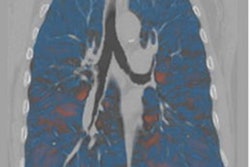

Quantitative CT (QCT) can capture inflammation patterns of bronchovascular bundle textures of the lung -- and thus help clinicians assess the severity of chronic obstructive pulmonary disease (COPD), researchers have reported.

While COPD inflammation typically begins in the large airways, "it progressively involves the small airways, lung parenchyma, and pulmonary vasculature, leading to remodeling of the bronchovascular bundles," the investigators explained. QCT texture analysis is increasingly used to identify structural and functional abnormalities in various lung diseases, and QCT texture biomarkers -- bronchovascular bundles and CT density gradient textures -- show promise for assessing the severity of COPD, since these markers are associated with systemic inflammation, impaired lung function, and all-cause mortality, they wrote.

Awan and colleagues investigated the efficacy of these QCT biomarkers for predicting poor COPD outcomes using data from the SPIROMICS (n = 2,981) and COPDGene (n = 10,305) studies. They tracked the two biomarkers as well as patient factors such as age, sex, body mass index, race, smoking status, smoking pack-years, presence of emphysema, and airway wall thickness as disease prognosticators.